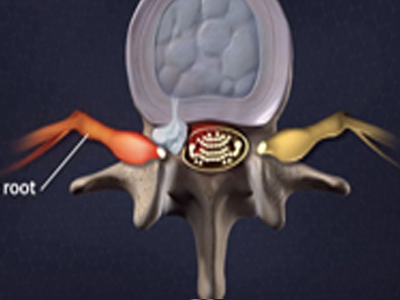

脊柱脊髓神经微创中心以微创技术为引领,以功能恢复为目标,主要治疗脊柱外伤、肿瘤、退行性病变、脊柱畸形等疾病。团队利用神经外科显微技术,结合神经内镜微创技术,对脊柱间盘变性疾病、颈腰椎管狭窄、颈腰椎间孔狭窄、颈腰椎间盘突出、颈腰椎体不稳、脊柱骨折、寰枢椎脱位、脊柱肿瘤、椎管内肿瘤、脊髓损伤、脊髓空洞、脊髓栓系等疾病进行高效、特色手术治疗,如颅颈交界区畸形寰枕减压内固定术、脊柱肿瘤全脊椎切除内固定术、微创椎管内肿瘤切除术、微创脊柱旁肿瘤切除术、寰枢椎脱位椎间融合内固定术、脊柱骨折微创经皮椎弓根钉内固定术、经椎间孔椎间融合内固定术(MIS—TLIF)等,最大程度降低脊柱脊髓手术创伤,具有创伤小、输血少、恢复快、口碑好,出院早等优势。